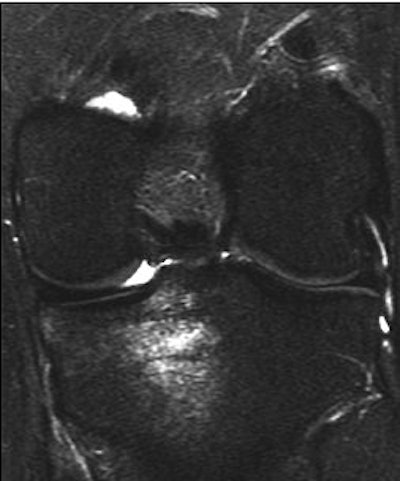

![]() |

| A 31-year-old man with fast resolution of bone bruise, reticular lesion type. Coronal T2-weighted fast-suppressed images (TR/TE, 12/3,700; fat saturation; section thickness, 3 mm; field-of-view, 180 x 135 mm; matrix, 385 x 224) show fast resolution of bone bruise from baseline (above), to three-week follow-up (middle), and at nine-week follow-up (below). |